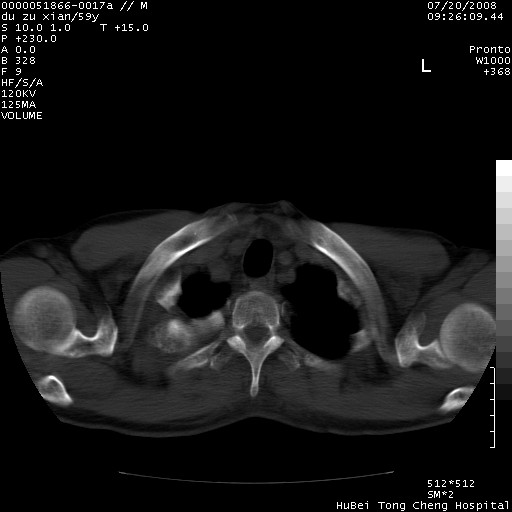

以下是引用宇宙ct在2008-8-25 23:21:00的发言:[br]右肺周围性肺癌并肋骨转移,纵隔淋巴结转移。

以下是引用zsl6918在2008-8-25 22:40:00的发言:[br]右肺周围性肺癌并肋骨转移,纵隔淋巴结转移。

以下是引用zy_zj在2008-8-26 15:24:00的发言:[br]单从病变本身,我倾向良性炎性病变,但肋骨转移了,所以说是考虑右肺周围性肺癌并肋骨、纵隔淋巴结转移可能性大。